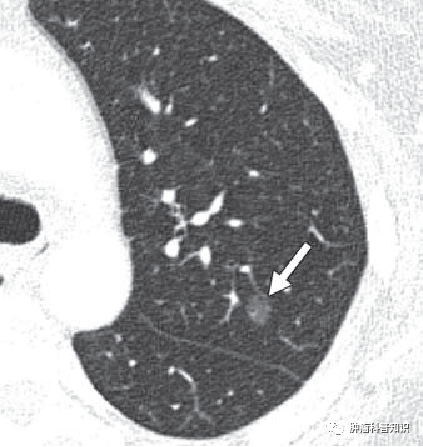

肺结节是指肺内直径小于等于3cm的圆形或不规则形态病灶。根据肺结节的密度可分为三种,实性结节,部分实性结节(也叫混合性结节),磨玻璃结节。当检查到肺结节后,也不必紧张,绝大多数肺结节是良性,肺结节常见的是一些良性病变,很少会发展为癌,绝大部分会自然消失。 然而临床上确实有一些结节存在着癌变风险,这一过程是漫长的,一般需要5-10年甚至更长。从肺泡上皮增生-不典型增生-原位癌-微浸润性腺癌-浸润性腺癌逐步生长。我们今天来看看肺结节的癌变的过程。

原位癌(AIS)

是指已经发生了癌变,但仅限于上皮层内,未突破基底膜,所以几乎没有任何症状。导致很多人都是在体检时发现,这个时候已经形成了能够看到的原位癌结节了。